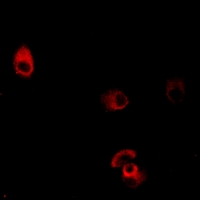

Immunofluorescent analysis of Dopamine Receptor D4 staining in MCF7 cells. Formalin-fixed cells were permeabilized with 0.1% Triton X-100 in TBS for 5-10 minutes and blocked with 3% BSA-PBS for 30 minutes at room temperature. Cells were probed with the primary antibody in 3% BSA-PBS and incubated overnight at 4 °C in a hidified chamber. Cells were washed with PBST and incubated with a AF594-conjugated secondary antibody (red) in PBS at room temperature in the dark.